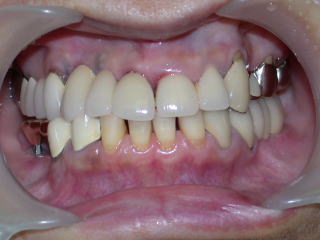

症例9:50歳代女性(新潟県長岡市要町 要町歯科 インプラント)

右上1、2、3が義歯ですが、見た目、装着感、発音など色々の不満があり、インプラントを希望しています。

こちらの患者さんは下顎両側臼歯部にもインプラントを入れており、インプラントの良い点をご自身で感じています。

上部構造物作製、試適、調整し装着しました。

患者さんは、義歯の不満が全て解除され、大変満足されており、当方も嬉しい限りです。